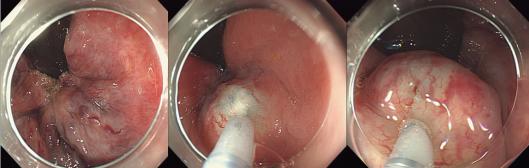

消化内科编制床位141张,年门诊平均就诊量约十万余人次,出院约6000余人次,内镜诊疗60000余人次,手术或治疗4千余例。我院地处川东北地区,长期收治不明原因腹水、不明原因消化道出血、不明原因腹痛、急性重症胰腺炎、肝硬化伴严重并发症及消化道大出血等疑难危急重症病人。作为川东北地区消化系统内科治疗的标杆,消化内科一直致力于示范和推广高水准的消化道诊疗技术,为提高诊疗技术,为广大患者提供更好的服务,我科购进了奥林巴斯小探头超声内镜、纵轴线阵扫描超声胃镜、奥林巴斯290色素放大内镜(NBI)、十二指肠镜、富士7000放大内镜、富士双气囊小肠镜等内镜下诊疗的高端设备。消化内科极其重视消化道肿瘤的早诊早治及消化内镜下一系列医疗技术,开展了EMR、 ESD、STER、POEM、EUS及内镜下止血等手术。同时,还大力开展消化放射介入治疗如ERCP等多项介入技术。消化内科联合急诊医学科、介入科、普外科等多科建立危险性消化道出血 MDT 团队,建立“危险性上消化道出血救治区域中心”,7×24 小时绿色通道,提供全面、优质诊疗方案,缩短危险性消化道出血急诊救治时间,大大提高了患者生存率。在临床工作中努力深化亚专科和各专业组建设,各专业组通过进修学习及各类学术交流、病例研讨等活动,不断提升团队整体实力,为患者提供更精准、更专业的医疗服务,努力在医学亚专业领域内实现新的突破与飞跃。

POEM治疗贲门失弛缓症

8. 贲门失弛缓内镜下括约肌切开治疗。